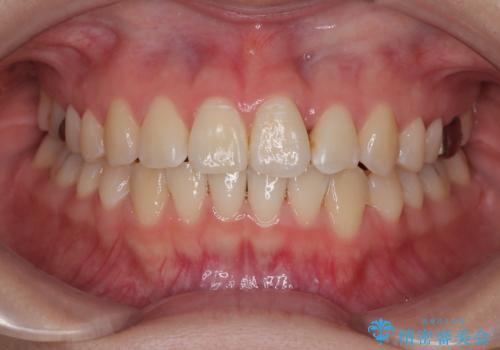

矯正治療期間はわずか10か月と、比較的短期間で終了しました。

前歯のデコボコがなくなり、見た目の印象が大きく変わっただけでなく、歯磨きがしやすくなり、むし歯や歯周病のリスクが大きく減少しました。